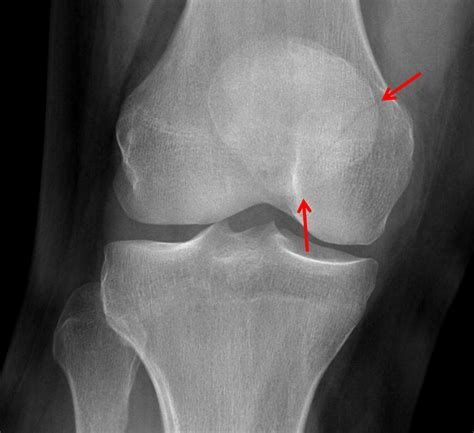

While only an X-ray or MRI can definitively diagnose a fracture, certain clinical signs are strongly associated with broken bones in the knee area. If you notice a combination of these, seek medical attention immediately.

When you arrive at the clinic or hospital, the medical team will likely perform a physical examination followed by diagnostic imaging. An X-ray is the gold standard for identifying fractures, but a CT scan may be required to assess the extent of the damage if the fracture extends into the joint space. Once the extent of the fractured knee symptoms is mapped, the doctor will determine whether non-surgical intervention—such as casting and bracing—or surgical fixation is required.